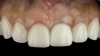

(19.) Four-month postoperative frontal and occlusal views revealing an ideal position of the tooth No. 9 margin in relation to its contralateral counterpart and an abundant amount of supracrestal soft tissue.

Figure 19

(20.) Four-month postoperative frontal and occlusal views revealing an ideal position of the tooth No. 9 margin in relation to its contralateral counterpart and an abundant amount of supracrestal soft tissue.

Figure 20

A patient presented for the restoration of an implant that had been placed at the site of tooth No. 9, which exhibited a residual soft-tissue deficiency and an undulating facial soft-tissue morphology (Figure 11). The objective of the treatment was to change the appearance and thickness of the facial soft tissue prior to crown placement to optimize the esthetics and prevent future soft-tissue dehiscence. After flap reflection (Figure 12), a graft was acquired from the patient's tuberosity to augment the supracrestal soft tissue (Figure 13). A volume-stable collagen matrix was then placed to further increase the thickness of the soft tissue adjacent to the implant body (Figure 14), and the flap was sutured closed (Figure 15). Following a 3-month healing period, a positive change in the soft tissue's morphology was apparent; however, its volume remained deficient when compared with that of tooth No. 8 (Figure 16). When the screw-retained crown was delivered, a second graft was acquired from the tuberosity and placed to further increase the volume of the supracrestal soft tissue (Figure 17 and Figure 18). A postoperative healing period of 4 months resulted in an ideal position of the margin of tooth No. 9 with regard to its contralateral counterpart as well as more natural looking soft-tissue morphology and excellent supracrestal soft-tissue thickness (Figure 19 and Figure 20). Eight months postoperatively, the position of the gingival margin and the thickness of the soft tissue had been maintained (Figure 21 and Figure 22).